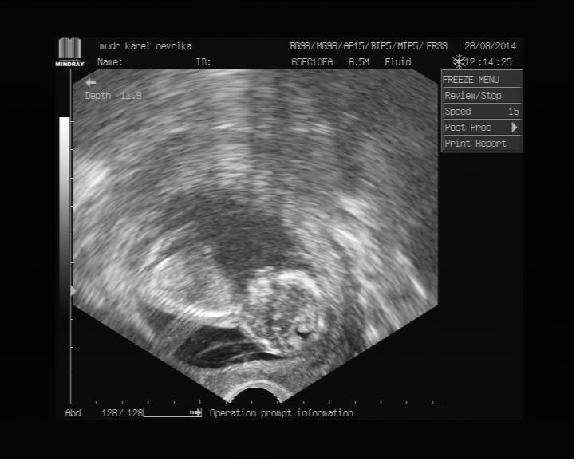

Holky a tady, je ani jsem nevěděla, že nám doktor poslal obrázek..:)